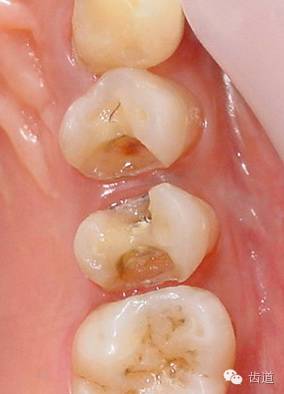

1、磨牙近中崩折舌面行嵌體牙體預(yù)備后

2、金屬鑄造嵌體

3、磨牙金屬鑄造嵌體粘固后